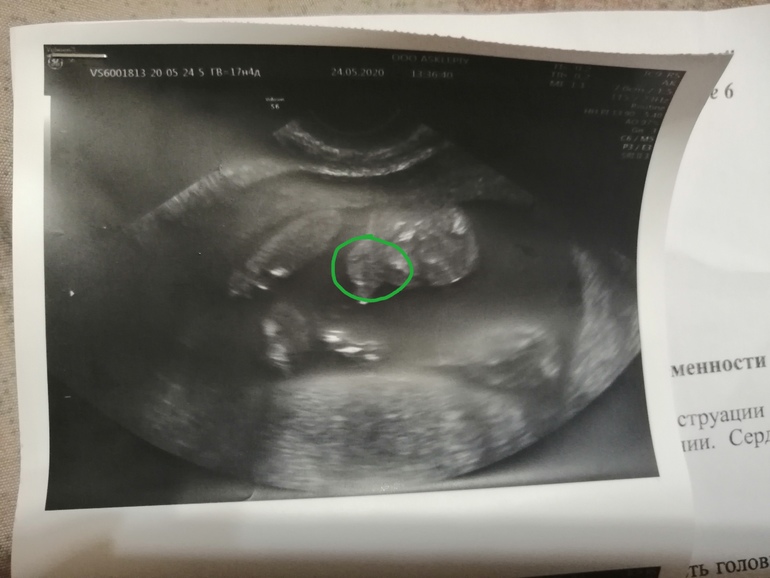

Пол малышаСделали узи на 17 неделе по животу увидел девочку, а вагинально мальчика.

Сделал фотку причиндалов.. Ну неужели это сверху такие большие яички и писюн? Кто понимает, помогите..

Я уже рассмотрела. Сверху голова, около неё рука, там прям пальчики просматривается. А снизу ноги в коленях согнутые. По ходу он мне сказал, что сделает фотку с половым и органами, а сам не сделал.

Я обвела, там прям кисть руки..

Рядом с головой. Если перевернуть фотку, то прям видно тонкие пальчики, как будто у рта, а снизу ножки, согнутые в коленях.

Извиняюсь, что мучаю вопросами.. Но просто все равно не совсем понимаю... Ножки согнуты в коленях.. И получается как будто животик и половые органы на одном уровне с коленками.. И живот для меня похож на лицо... Бредовая фотка все таки... 😀😀😀

Может я путаю снимки и тут просто малыш.. Голова и согнутые ножки.... Лицо.. Тело не видно, так как он в позе невыпрямленного тела и ножки нижняя часть... Ой с ума сойдешь.

Вот и я не понимаю... Просто он сказал, что сделает на память половые органы.. Я даже не просила.. Ну я сначала и подумала, что сверху это яички и пися.. Но сейчас смотрю и думаю.. Разве может быть такое расстояние между ногами...

Ну, я вижу на Вашем фото что-то похожее на мошонку и членик)) Но вот оно ли))

Ну, я вот на Вашем кадре смотрю на то, что обвела (уж извините, что стащила для редактирования - я удалю, мне чужого не надо

Просто, чтобы показать, куда смотреть), и вижу мошонку и писюн. С первого взгляда не сразу поняла. Но остальное что и где - не разберу. Да, фотка и правда чуднАя))

Теперь мне кажется, что на фото ножки, согнутые в коленях.. Затем дальше пустота, так как тело все же в положение полусогнутом, и голова лицом вперёд... А половых органов нет... Может он вообще не сделал то фото, а я ищу половые органы...

Наверно все же на этой фотке просто малыш.. Голова и ножки, и ручка около головы...